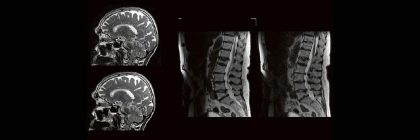

Professor Dr. med. Marc Brockmann WEITERENTWICKLUNGEN VON KOPF BIS FUSS BEIM VC Oberstarzt Dr. med. Stephan Waldeck DEEP-LEARNING-REKONSTRUKTION IN DER NEURORADIOLOGIE Die CT ist ein essentielles Routine-Verfahren in der Neuroradiologie. Weiterlesen …